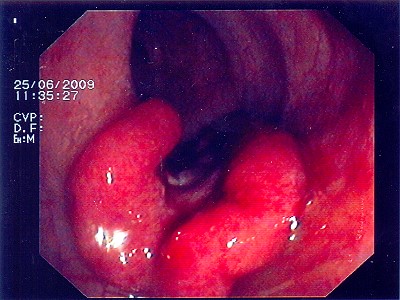

Abb. 2: Das Gebilde des oberen Mastdarmes, auch hier ist die Ent- fernung des Tumors mittels Darmspiegelung nicht mehr möglich. Abb. 2: Das Gebilde des oberen Mastdarmes, auch hier ist die Ent- fernung des Tumors mittels Darmspiegelung nicht mehr möglich.